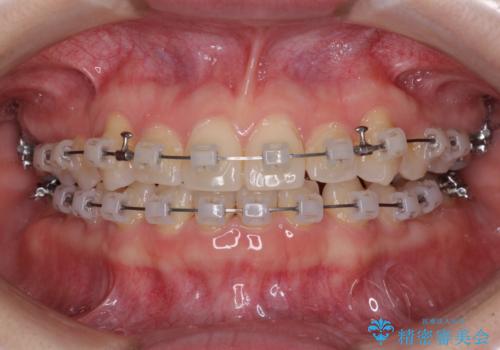

- クリアブラケット

- 1年3ヶ月

- 10-30回

- 八重歯を気にして来院された患者様です。

口腔内の状況を確認したところ、左右ともに下顎第二大臼歯が欠損しており、咬み合うべき上顎の第二大臼歯が著しく挺出していました。

挺出した大臼歯を元の位置に戻すことは現実的に難しいため抜歯することとし、補助装置とワイヤー装置により上顎歯列全体を後方に移動することとしました。

順調に後方移動することができ、わずか1年強で治療を終えることができました。